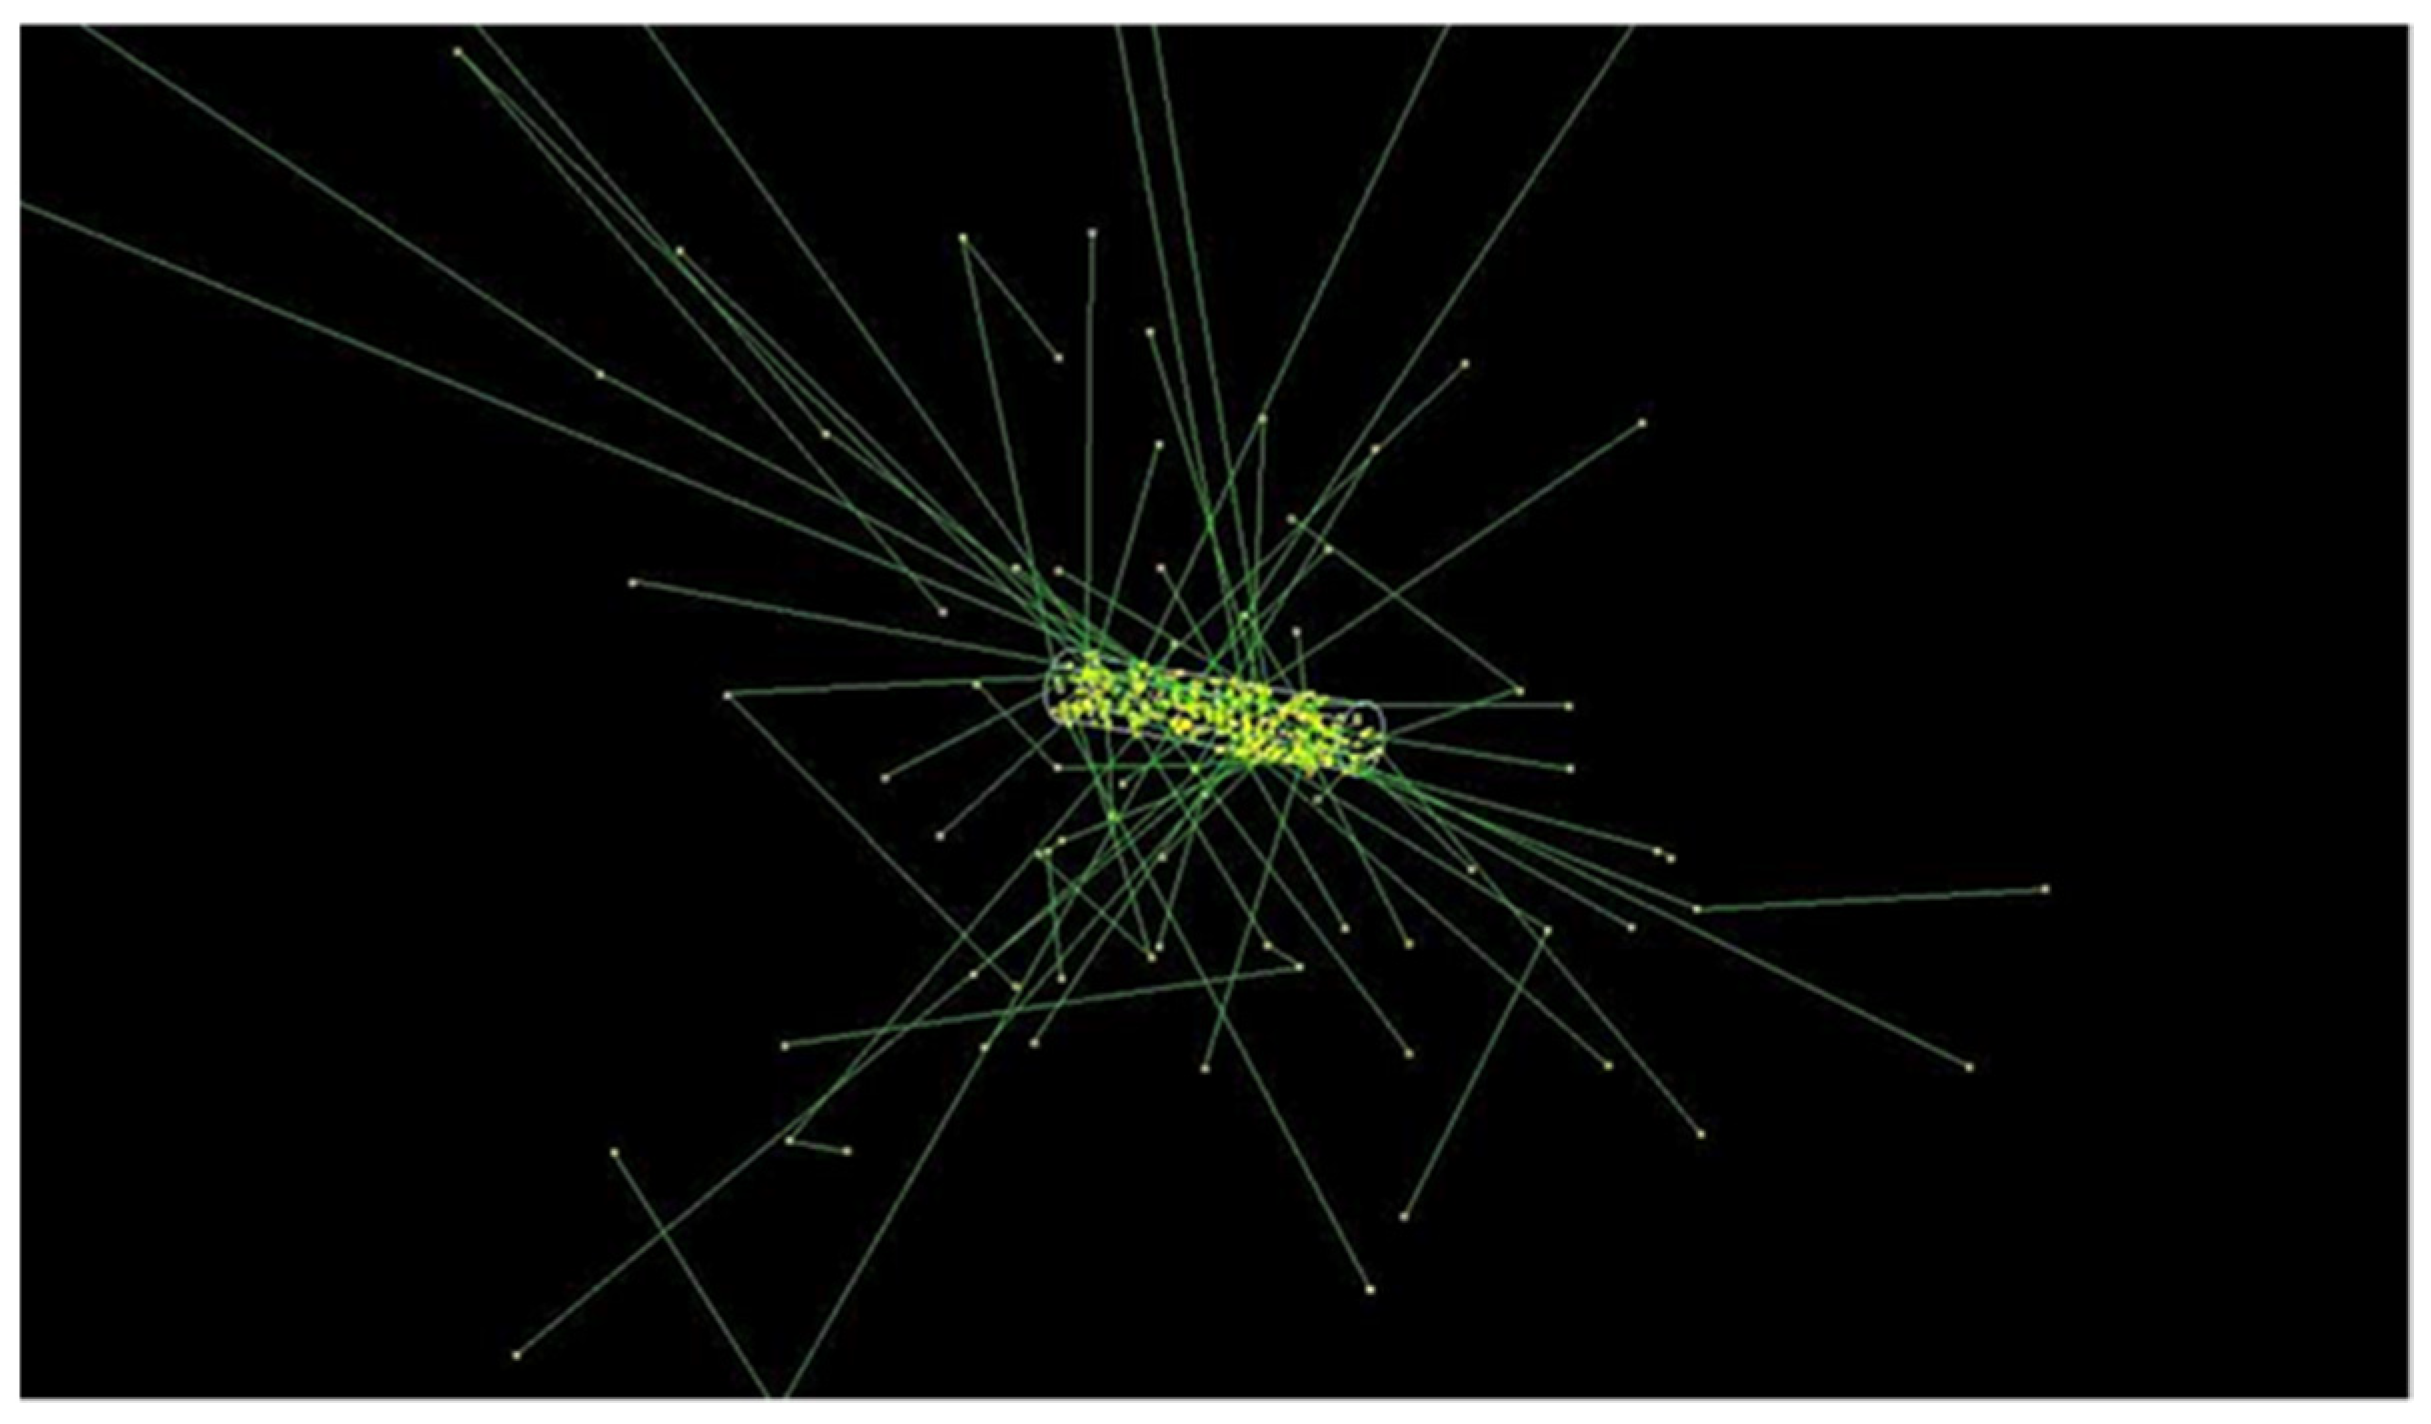

2.3. Brachytherapy Seed Simulations

3.2. Radioactive Magnetic Nanoparticle (RMNP) Seed